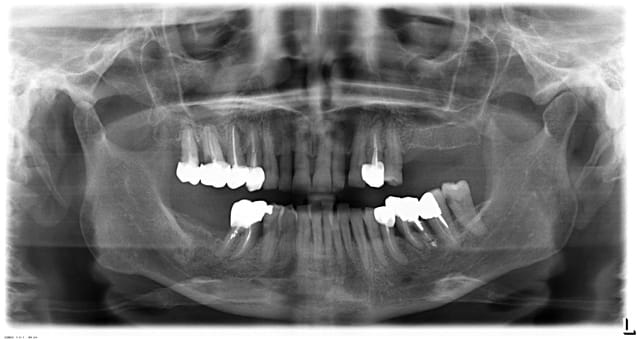

Comment soigneriez vous cette patiente qui est venue me consulter pour une cellulite au niveau de 14 et 15.

La patiente de 60 ans est en bonne santé générale et fume 10 cigarettes/jour.

....quoique tu fasses sur 14 et 15, il me semble que 16 et 17 sont condamnées....

++1, et 36 condamné aussi en plus de 14-15-16-17-